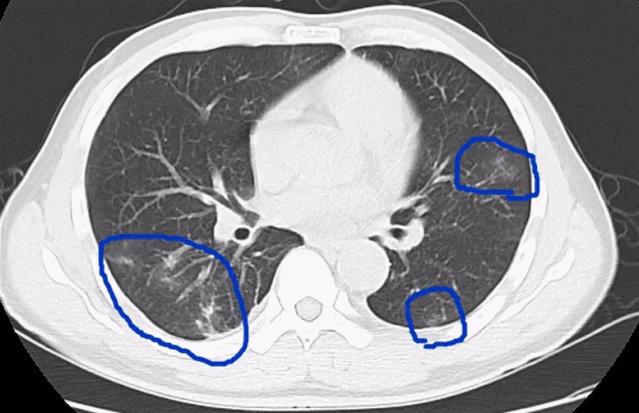

去年9月,深圳的一家3口先后发热、腹痛、腹胀、乏力、食欲下降、干咳等。去医院检查发现,3人的血常规中嗜酸性粒细胞明显升高。医院给他们做了寄生虫抗体、CT检查后,发现这一家人得的是“肺吸虫病”。

肺部不舒服。并殖吸虫寄生在肺部,会引起 咳嗽、胸痛、咳出铁锈颜色的痰 ;有虫子在腹腔脏器间“跑来跑去”,让你 腹痛、腹泻、恶心、呕吐等 ,还可能侵犯肝脏导致 肝功能异常; 如果虫子侵入大脑,会 头痛、头晕、癫痫 等;看到皮肤下有 结节或包块。 而且这包块还会“乱跑”,可能今天出现在背部下面,明天就游到背中部了。

示意图,图文无关